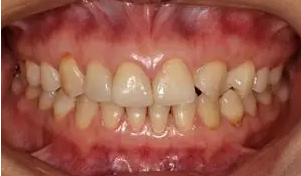

術(shù)前全牙弓非咬合照

病例分享|復(fù)合樹脂微創(chuàng)美學(xué)修復(fù)關(guān)閉上前牙間隙

術(shù)前上前牙正面照